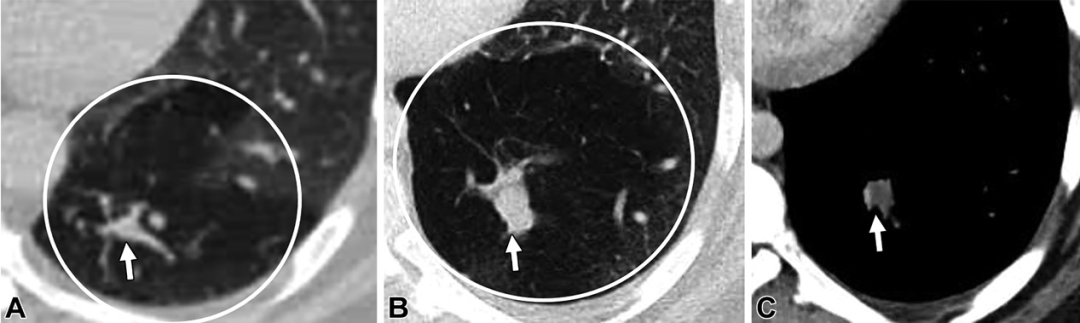

肉芽肿。36岁男性。轴位CT图,可见簇状结节(白色圆圈),中心呈高密度,外周可见小动脉(白色箭头)。以上表现最提示肉芽肿。后续基因检测及头颅磁共振均为阴性,患者也没有遗传性出血性毛细血管扩张症的家族史。

肉芽肿。31岁男性,有遗传性出血性毛细血管扩张症家族史。(A至C)轴位CT增强图,可见左肺下叶病变,伴供血动脉(白色箭头)以及中心高密度(白色星号),未见引流静脉。(D)随诊CT5年后,病变变小(白色星号),开始钙化。提示肉芽肿。

肉芽肿性病变。38岁女性。(A,B)轴位CT增强图,无强化的结节(白色箭头)伴多发邻近的卫星结节(黑色圆圈)。(C)轴位最大密度投影图,可见供血动脉(黑色箭头)及多发卫星结节(黑色圆圈),未见引流静脉或病灶。以上表现符合肉芽肿性病变。